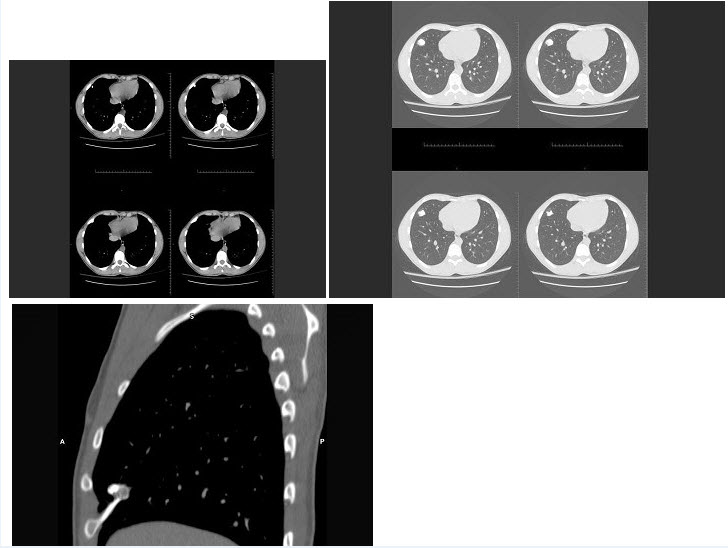

31、单项选择题

女,35岁,咳嗽,咳痰,发热3月余,胸部CT如图,最可能的诊断为()

A.类风湿肺炎

B.红斑狼疮性肺炎

C.间质性肺炎

D.肺结节病

E.肺部感染

点击查看答案

本题答案:微信扫下方二维码即可打包下载完整带答案解析版《★放射医学(医学高级)》或《放射医学(医学高级):CT》题库